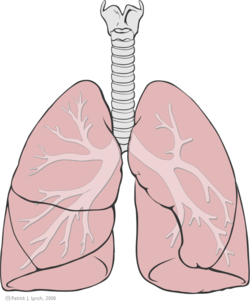

القصبة الهوائية أو الرغامى هي أنبوب غضروفي يربط الحنجرة بالحويصلات الهوائية في الرئتين، لتتيح مرور الهواء، ولذلك فهي موجودة تقريباً في كل رئات الحيوانات. The trachea extends from the larynx and branches into the two primary bronchi. At the top of the trachea, the cricoid cartilage attaches it to the larynx. The trachea is formed by a number of horseshoe-shaped rings, joined together vertically by overlying ligaments, and by the trachealis muscle at their ends. The epiglottis closes the opening to the larynx during swallowing.

قطر القصبة عند الإنسان 2.5 سم، وطوله 13 سم تقريباً. تنقسم القصبة لنصفين، الأول يقع في العنق والآخر في الصدر. يوجد عدد من الغضاريف التي تساعد على الحفاظ على فتحة القصبة الهوائية. في النهاية تتشعب القصبة لجزئين يذهب كل منهما إلى إحدى الرئتين حيث يصل الهواء.

The trachea's main function is to transport air to and from the lungs. It also helps to warm, humidify, and filter the air before it reaches the lungs.